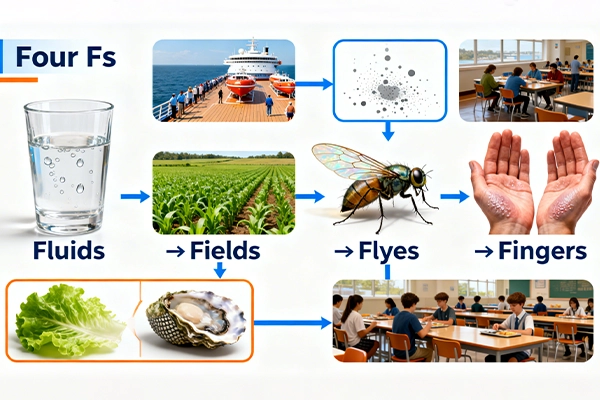

Norovirus is infamously contagious—even a tiny amount of the virus (fewer than 20 particles) can cause infection. Its primary transmission route is fecal-oral, meaning it spreads when people ingest tiny particles of stool from an infected person. This can happen through four common pathways, known as the “Four Fs”:

- Fluids: Contaminated drinking water (e.g., from polluted wells or untreated sources).

- Fields: Contaminated soil or crops (e.g., when infected stool fertilizes agricultural fields).

- Flies: Insects that land on infected waste and transfer particles to food or surfaces.

- Fingers: Hand-to-mouth contact after touching contaminated surfaces (e.g., doorknobs, phone screens, or shared utensils).

The virus also spreads via vomit droplets (released when an infected person vomits) and contaminated food—especially uncooked items like leafy greens and shellfish. It thrives in close quarters, which is why outbreaks often make headlines in: